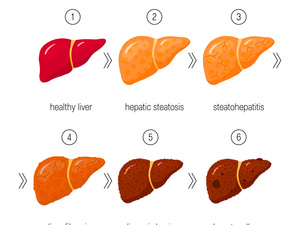

第四代试管婴儿是指:通过获得女性卵巢中的卵母细胞,从中提取到线粒体,并将其注射到其成熟卵子之中,大幅度提高卵子的质量。线粒体存在于大多数细胞当中,作用为“细胞能量的发源器”,卵子干细胞作为一种未充分分化,尚不成熟的细胞,有生长成为新的、成熟的卵子的潜能。所以,将卵子干细胞的线粒体注入试管婴儿周期所取得的成熟卵子当中,可以使后者的质量得到极大提高,产生更多基因正常的胚胎。